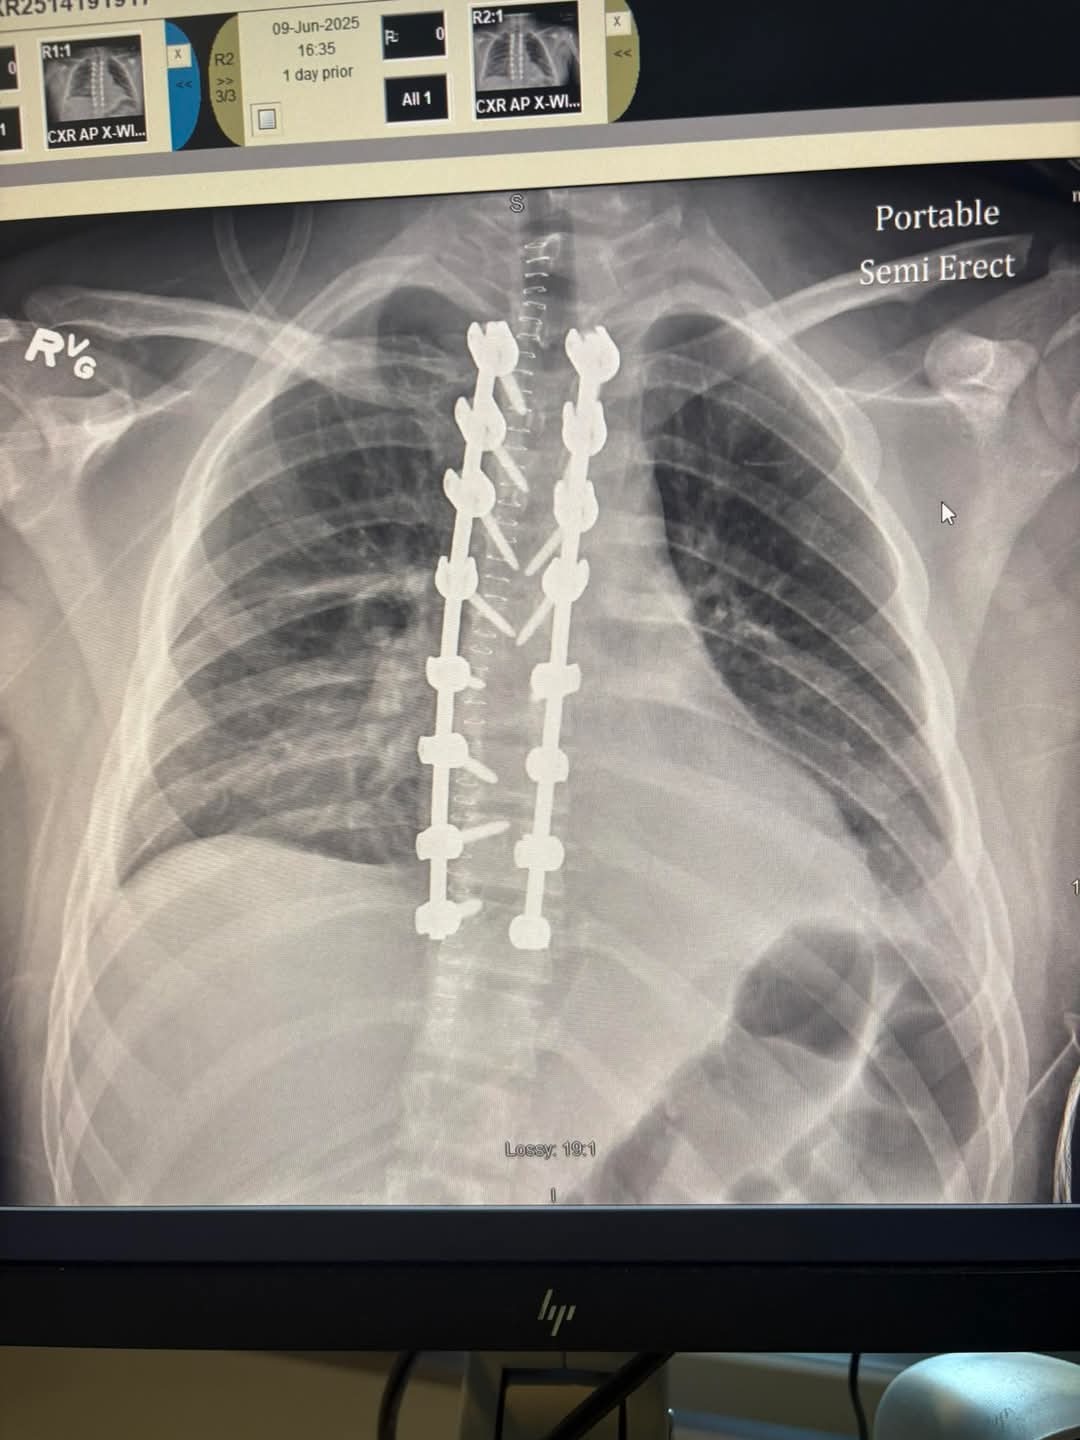

He went into emergency surgery the morning of the 9th which gave us the best of the best drs and surgeons. They placed a rod with screws in his back that stretch from T3 to T10. With that surgery they were able to relieve the pressure off his spine which will help with recovery. He was extremely doped up and doesn’t remember much.